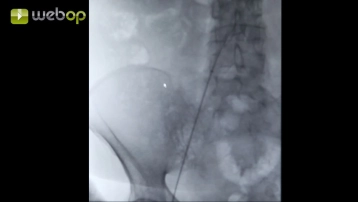

Punção da artéria femoral comum direita

Anestesia por infiltração na virilha direita com Xylonest 1%. Palpação e punção da artéria femoral comum. Inserção de um fio Terumo® através da cânula de punção.